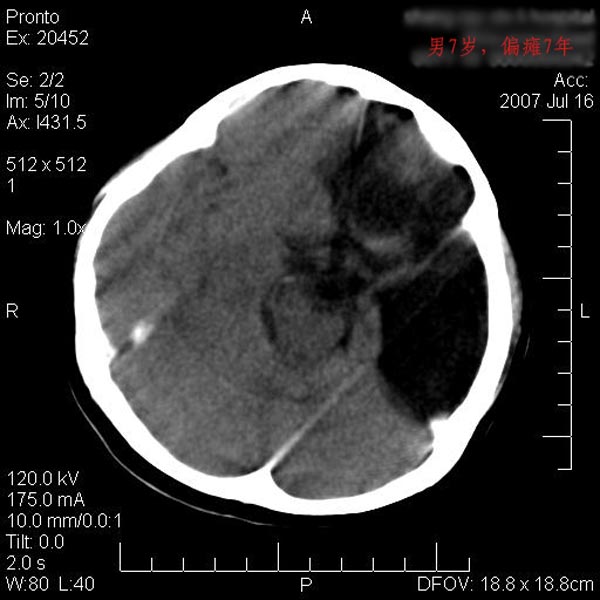

男性 7岁:偏瘫7年,出生时脑内出血。

左侧大脑半球发育不良、软化灶伴穿通畸形形成。

左侧脑叶体积缩小。密度减低,左侧脑室牵拉扩大并向左移位,左侧脑室颞角与侧裂池相通并呈囊性扩张。考虑左侧大脑发育不全,软化灶并穿通畸形。

左侧颅腔变小,左侧大脑半球体积缩小密度减低,呈负占位效应,左侧侧脑室扩大,出生时有脑出血病史。多考虑先天因素,左侧大脑前、中动脉起始部狭窄或闭塞,即烟雾病可能性大。